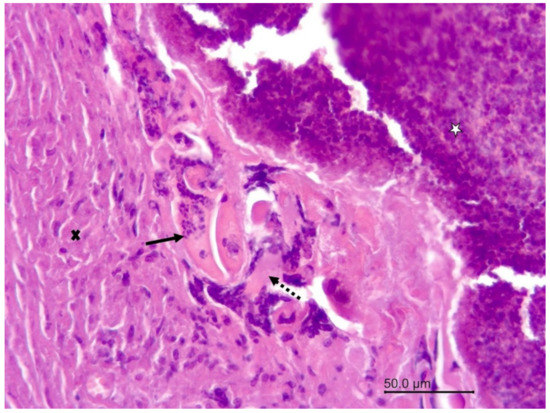

3.1.2. Necropsy and Histopathology

3.2.1. Necropsy and Histopathology